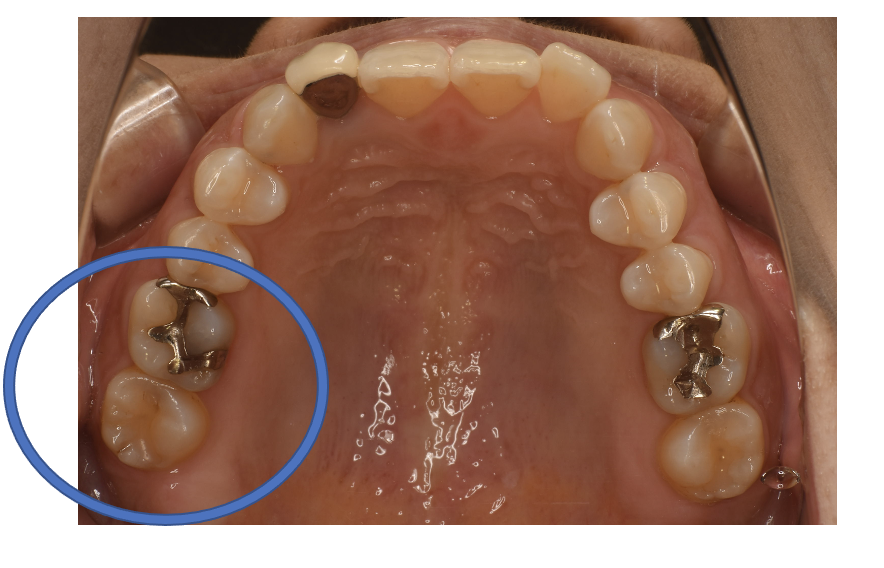

フルジルコニアIn 1 +フルジルコニアCr NO.25

Before

After

| 治療方法 | フルジルコニアCr、In 虫歯などで失った歯質を天然歯と同じ色・質感のセラミックの一種であるジルコニア(人工ダイヤモンド)で補う治療法。 変色がなく耐久性の高い治療ですが、歯周病や二次虫歯を予防するためには歯科医院での定期的なメインテナンスが大切です。 |

| 治療のデメリット | 変色がなく耐久性の高い治療ですが、歯周病や二次虫歯を予防するためには歯科医院での定期的なメインテナンスが大切です。 |

| 費用 | ¥89,000、¥69,000 |

| 通院回数 | 1ヶ月〜6ヶ月 |

| 備考 | 院長より 銀歯と、プラスチックで修復してあった2本の歯の再発虫歯の症例です。銀歯との境目から虫歯が進行していた手前の歯は、内部で虫歯が進行していたのと噛み合わせが強く、ヒビが入っていたので、コーティングして、ジルコニアCrで被せて守っています。 一番奥の歯は、内部で虫歯が進行していましたが、部分的な詰め物で対応できる範囲でした。しかし、噛み合わせが強いので、ジルコニアInで修復しています。 |